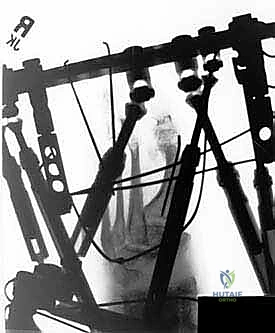

Now for the delicate process of threading the Gigli saw. I take a No. 2 Ethibond suture and, using a curved tonsil hemostat, pass it through the plantar tunnel from Incision 1 to Incision 2. Next, from Incision 3, I pass the tonsil subperiosteally to Incision 2, grasp the suture, and pull it dorsally. We tie one end of the Gigli saw securely to the Ethibond suture. With gentle, steady tension, we pull the suture back through Incision 2 towards Incision 3, drawing the Gigli saw from medial to lateral, subperiosteally, across the dorsum of the foot. Finally, passing the tonsil from Incision 4 to Incision 3, we grasp the free end of the Gigli saw and pull it out laterally. The saw is now circumferentially positioned around the midfoot bones. We mandate a fluoroscopic check here to ensure the saw has not migrated from our marked osteotomy level.

We attach the T-handles to the Gigli saw. Using a smooth, reciprocating, long-stroke motion, we begin cutting the midfoot bones from medial to lateral. The motion must be controlled; aggressive, short strokes generate excessive thermal energy. As the saw approaches the lateral side of the foot, just before it completely exits the bone laterally, I take a periosteal elevator. I place it between Incision 4 and Incision 1, crossing over the Gigli saw. This elevator acts as a shield to protect the peroneal tendons and sural nerve as the saw breaches the lateral cortex, preventing catastrophic soft tissue laceration.

External Fixation Application

With the osteotomy complete and the deformity mobilized, we proceed to external fixation. The specific frame construct depends on the deformity, but typically involves a tibial block (two rings) and a foot block. The foot block usually consists of a half-ring or U-plate securing the calcaneus with opposing olive wires, and a forefoot half-ring securing the metatarsals.

Smooth 1.8-mm Ilizarov wires are passed under fluoroscopic guidance, ensuring bicortical purchase. We utilize olive wires to provide interfragmentary compression or to translate osseous segments. Crucially, wire insertion must be meticulously performed to avoid thermal necrosis: we pulse the drill, frequently clear bone debris, and immediately cool the wire with sterile saline. Once positioned, the wires are attached to the rings and tensioned to 110-130 kg using a dynamometer, transforming the flexible wires into rigid structural beams. If acute correction is planned, the deformity is manually reduced, and the frame is locked. If gradual correction is required (due to severe soft tissue contractures), hinges and compression/distraction rods or hexapod struts are applied, and the patient will begin turning the struts postoperatively following a brief latency period.